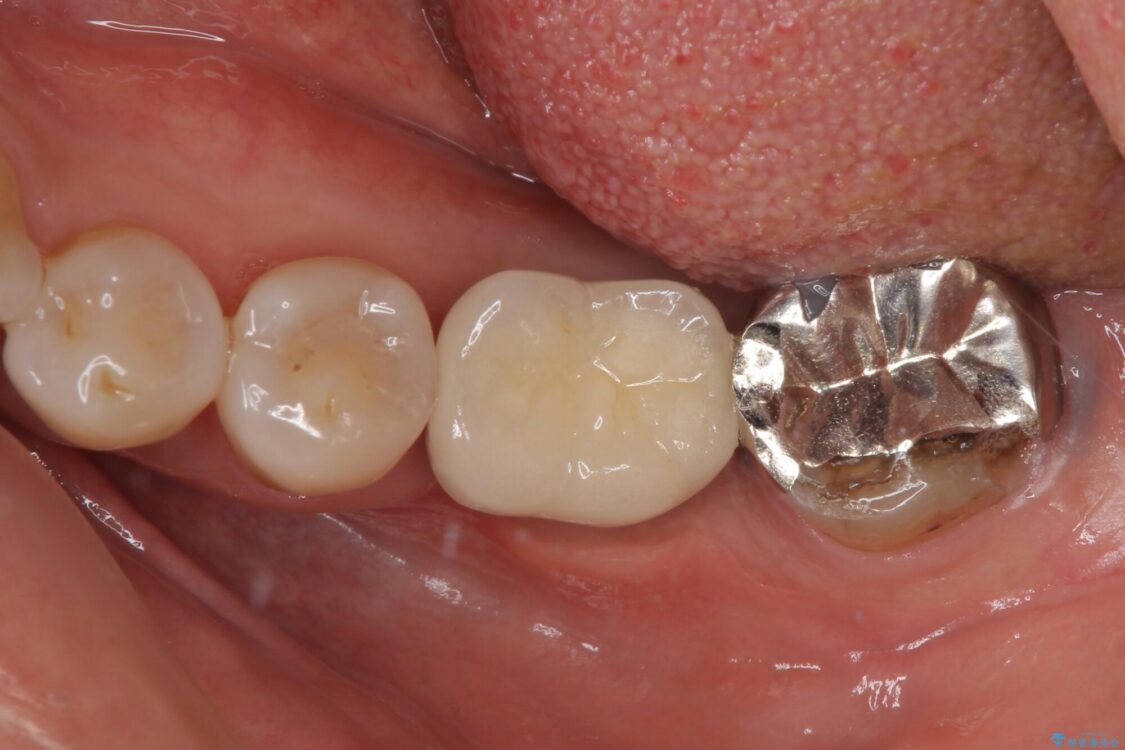

仮歯に変えた時点でしみる症状はなくなり、オールセラミッククラウンはまるで自分自身の歯のような舌触りとなり、大変満足していただきました。

• しみる奥歯 オールセラミッククラウンによる補綴治療 治療後画像